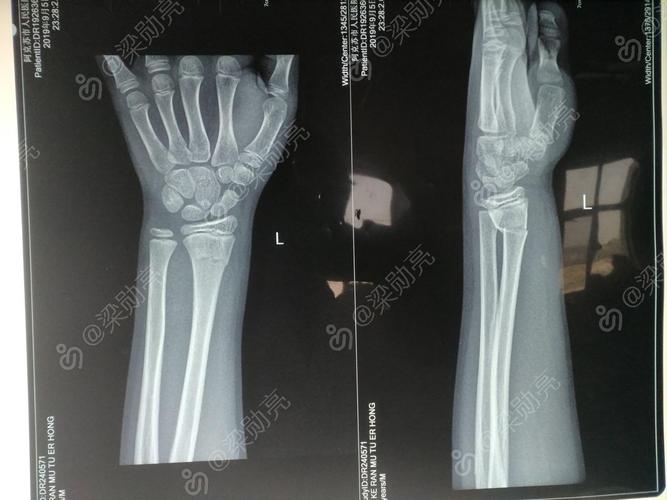

桡骨远端是指哪个位置,右桡骨远端骨折图片

右桡骨远端骨折图片

左桡骨远端骨折图片

正常桡骨远端骨折图片